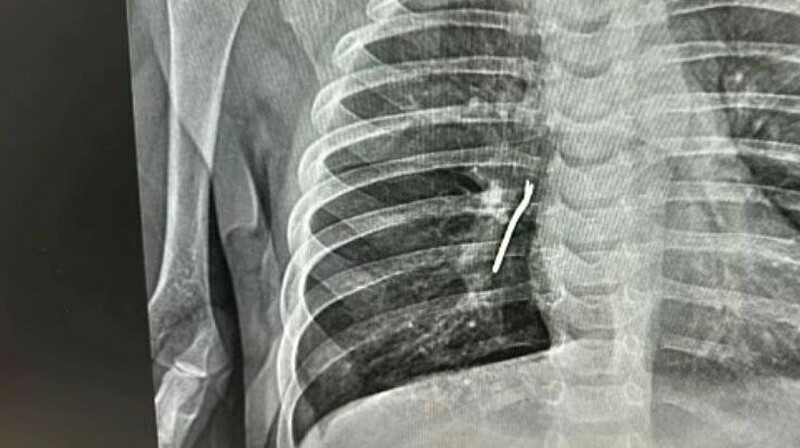

Алматылық дәрігерлер науқастың жүрек тамырларының қанмен қамтамасыз етілуін қалпына келтірді. 64 жастағы науқас ауыр жағдайда кардиологиялық орталыққа жеткізілді. Коронарография өткізілгеннен кейін әйелдің үш тамырының 99%, 95% және 85%-ға ауыр зақымданғаны анықталды, - деп хабарлайды Arbat.media.

Кардиохирургтар науқастың қан тамырлары шунтты орнату үшін өте жұқа болғанына байланысты оған аортокарональды шунттау отасын жасай алмады.

Консилиумде тамырларды стенттеу туралы шешім қабылдады. Іске интервенциялық кардиологтар кірісті.

Консилиумға қатысқан Алматы Қалалық кардиологиялық орталығының рентгенхирургия бөлімшесінің меңгерушісі Оразбек Сахов қан тамырларын стенттеуді жүзеге асырды.

Процедураның қауіптілігі мен күрделілігіне қарамастан, ол үш тамырдың екеуінің өткізу қабілеттігін қалпына келтіріп, пациенттің сауығуына мүмкіндік берді. Бұл зергерлік ота жергілікті анестезиямен 50 минутқа созылды.

"Ота пациенттің қан тамырларының өткізгіштігін қалпына келтіруге болатын қабылдау арналарының тарылуына байланысты қиын болды. Ота кезінде пациенттің қабылдау арнасын толық ашып, екі үлкен тамырды қалпына келтірдік, бірден екі стент орнаттық. Стенттеу нәтижесі өте жақсы болып шықты және науқастың жағдайы айтарлықтай жақсарды. Әйелге үшінші тамырды қалпына келтіру үшін тағы бір ота кейінірек жасалады", - дейді Оразбек Сахов.

Алматы Қалалық кардиологиялық орталығының интервенциялық кардиологтарының жоғары кәсіби құзыреттілігінің арқасында бүгінгі таңда науқастың денсаулығына еш қауіп жоқ.